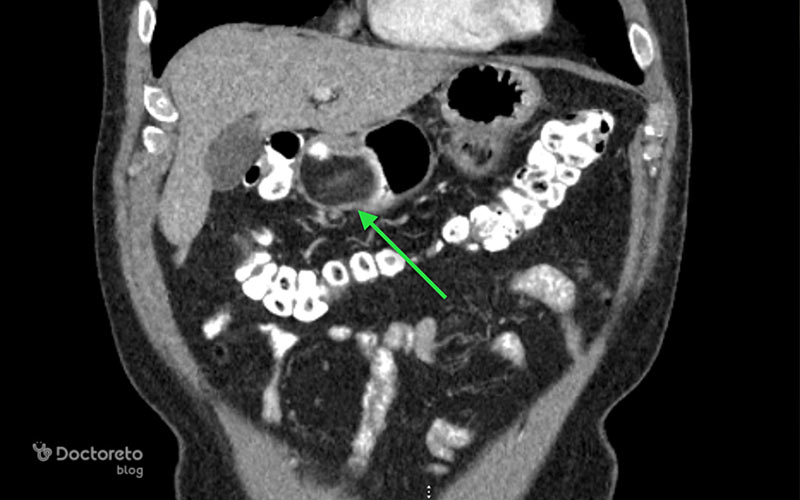

عکس تصویربرداری های سرطان معده خوش خیم

تصویربرداری پزشکی مانند سیتیاسکن و MRI به پزشکان کمک میکنند تا موقعیت، اندازه و ماهیت تومورهای معده را بررسی کنند. در ث تومورهای خوشخیم نیز این روشها کاربرد دارند تا احتمال نفوذ به بافتهای مجاور یا تبدیل احتمالی به بدخیم بیشتر و با دقت بالاتر ارزیابی شود. عکس این بخش نمونهای از این نوع تصویربرداریها را نشان میدهد.

عکس سی تی اسکن سرطان معده خوش خیم

سیتیاسکن ابزار قوی دیگری برای ارزیابی تومورهای معده است. این روش تصویربرداری به ویژه در تشخیص اندازه، موقعیت و ارتباط آنها با ساختارهای اطراف کاربرد دارد. حتی برای سلولهای خوشخیم سرطانی هم سیتیاسکن اطلاعات ارزشمندی در مورد چگونگی رشد و وضعیت بیمار ارائه میدهد. استفاده از این تصاویر کمک میکند تا پزشک نگاهی دقیقتر به تومور معده داشته باشد.